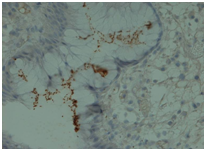

Antral biopsies revealed a moderate, chronic gastritis positive for H. Pylori (Figure 5). There was no evidence of malignancy but foveolar hyperplasia and cystically dilated foveolar glands consistent with Menetrier’s Disease (Figure 6).

Figure 5Antral biopsies staining positive for H. Pylori.